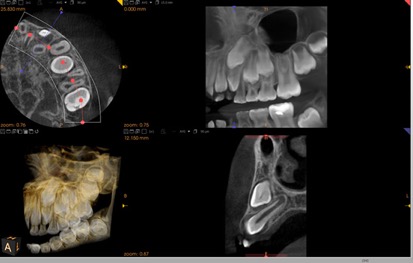

歯科用CT

従来のフィルムを使用したレントゲン撮影に比べ、人体に受ける放射線の量を約1/4~1/10に抑える事が可能です。

3次元歯科用CTを設置している歯科医院は、決して多くありません。

この歯科用CT(パノラマと3Dセンサーを駆使した回転式デジタルレントゲン)は

CTは立体的な画像・断層写真が写し出されます。

インプラントの診査・歯周病の程度・親知らずの状態の把握を正確に行うことができ、より安全、確実に治療することができます。

どんな画像が映し出されるの?

お子様の歯並びの萌出方向を調べたり

顎が開きにくい、関節雑音が鳴る方や

ご自身の顎顔面の形を総合的に診査できます!!